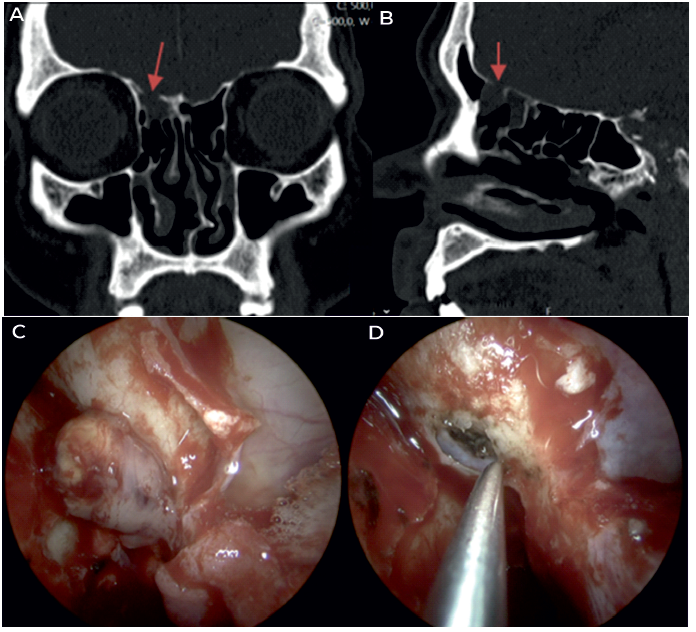

Figuras Caso clínico de meningoencefalocelo espontâneo da transição da parede posterior do seio frontal para a fóvea etmoidal direita. A e B. TC-SPN pré-operatória (seta - defeito ósseo); C. imagem intra-operatória da herniação; D. campo cirúrgico após redução com cauterização bipolar e exérese, destacando a importância da identificação do limite ósseo do defeito em toda a circunferência e o descolamento da dura na face intracraniana para permitir a colocação de material de reconstrução underlay